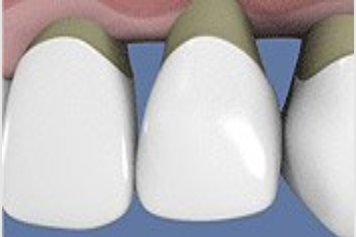

FICHE CLINIQUE Prothèse fixée conventionnelle : Couronnes et bridges